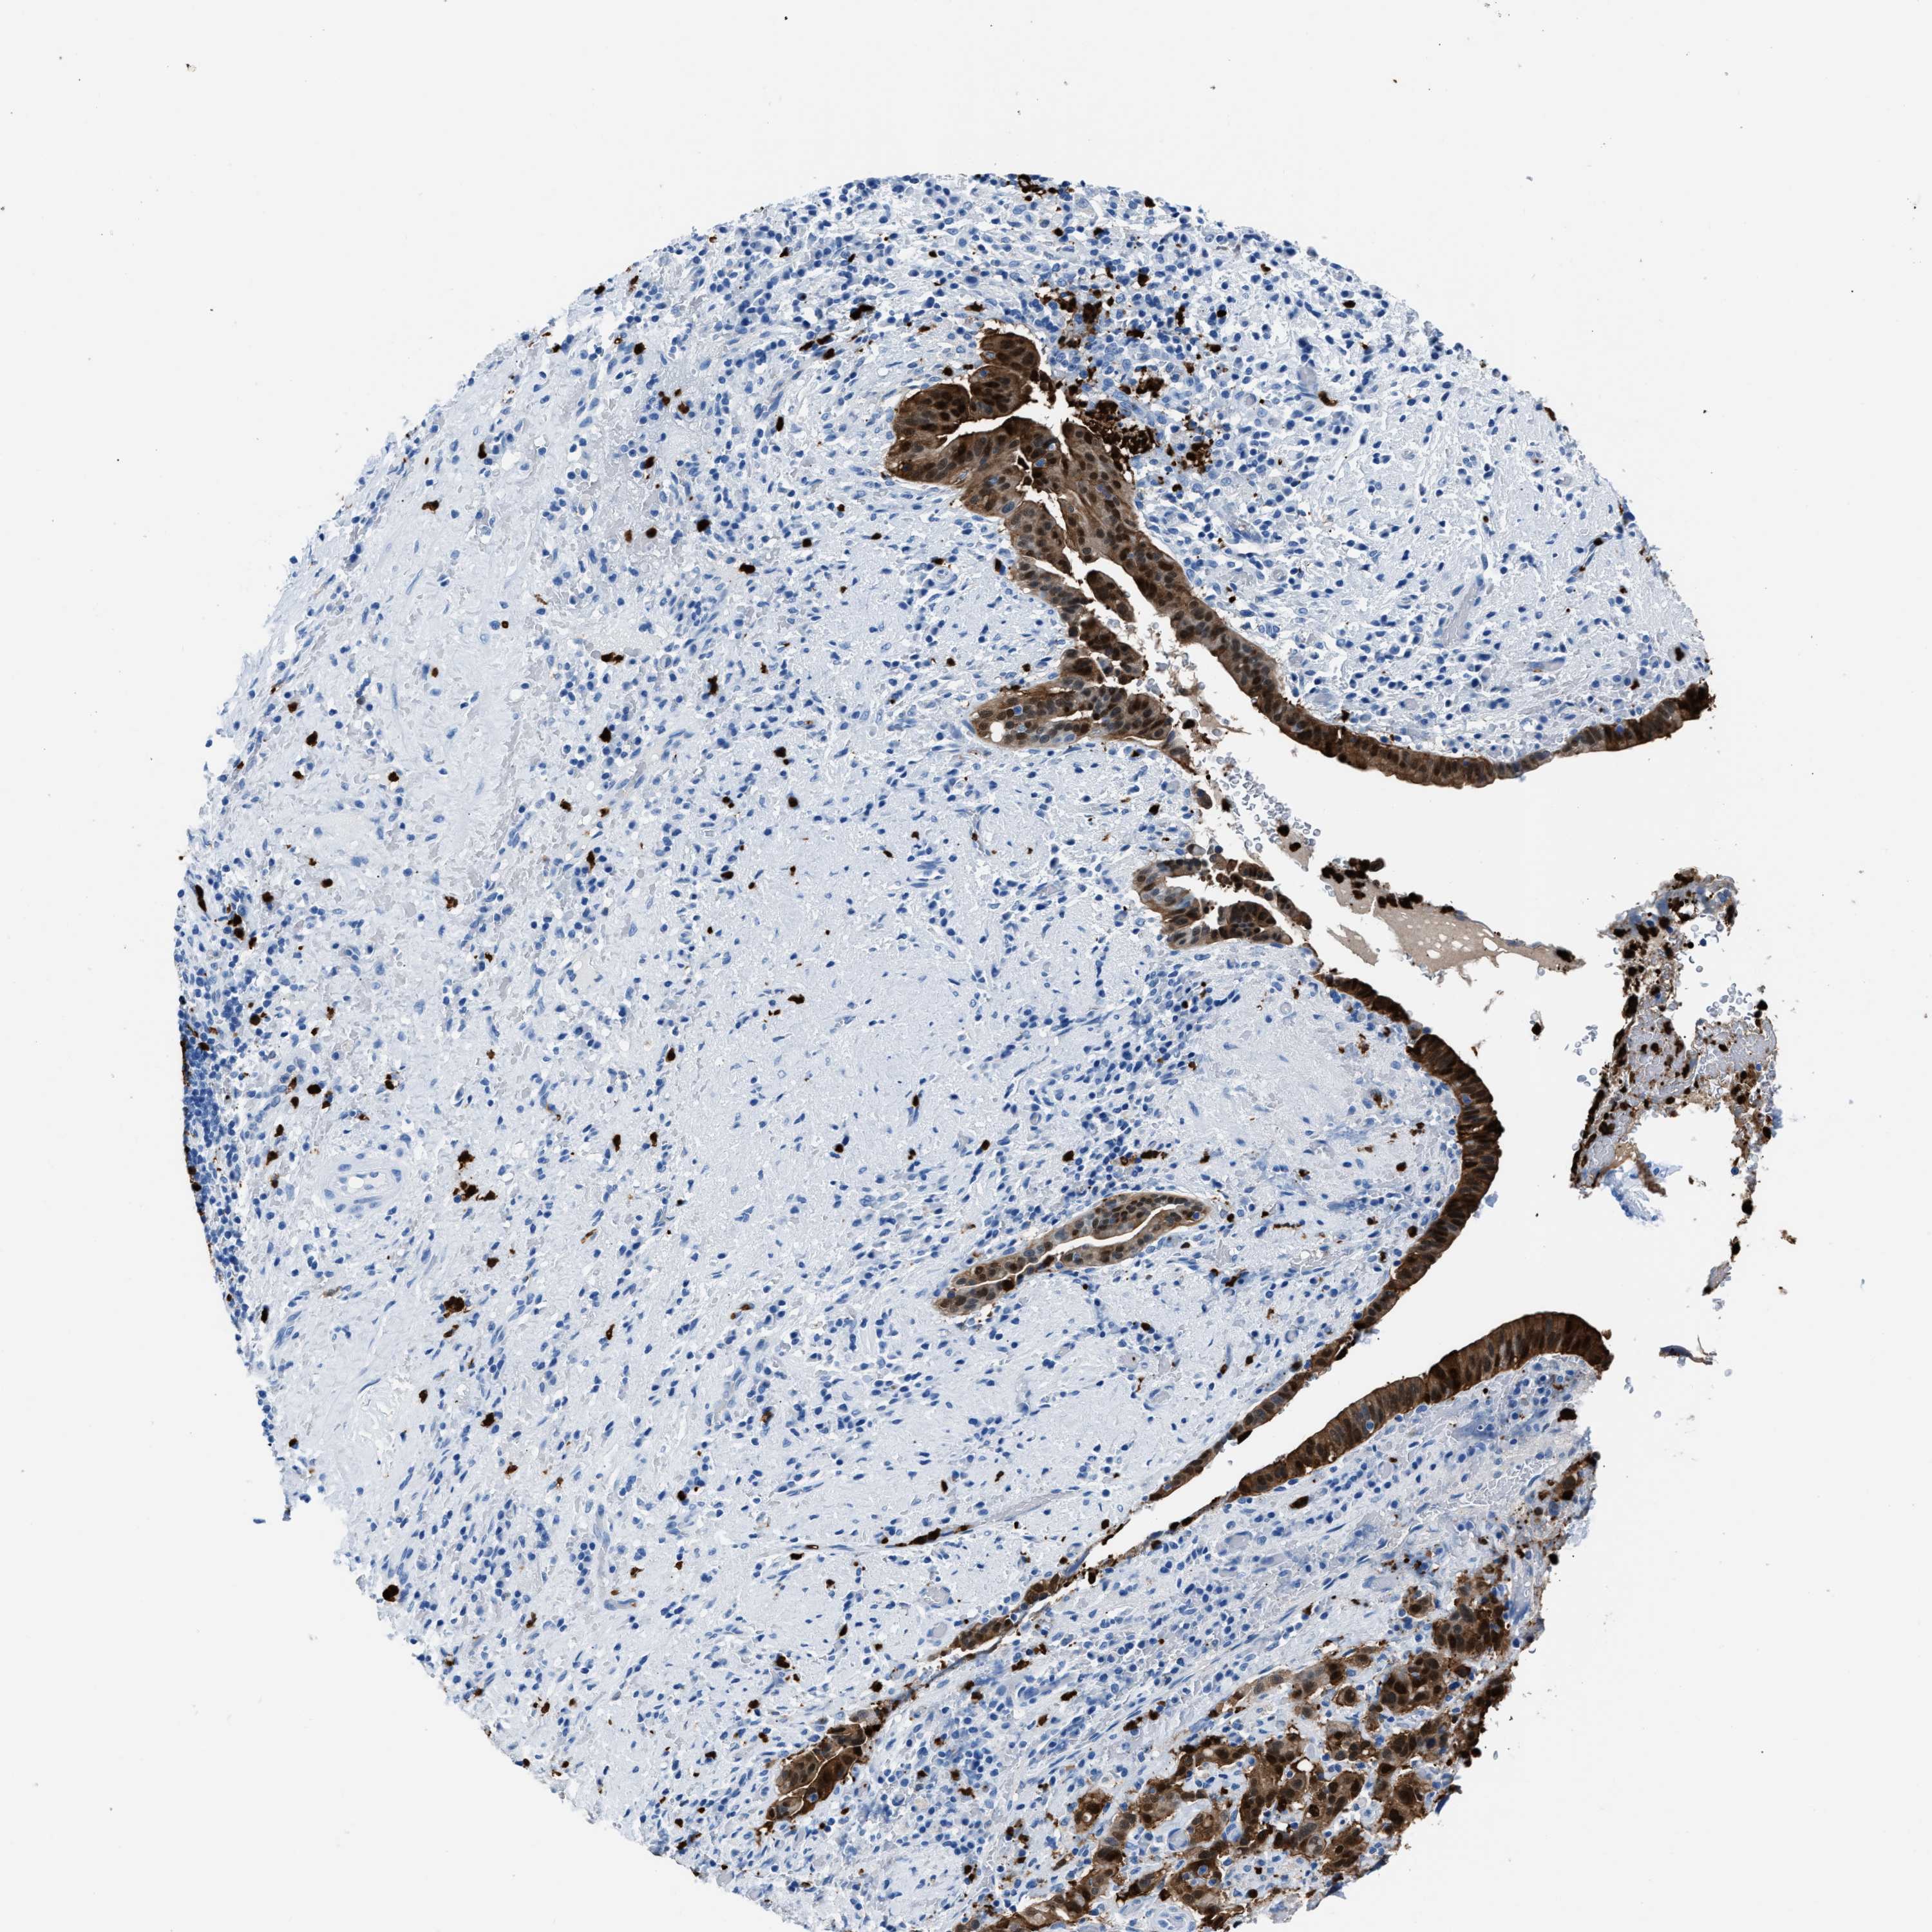

LIVER CANCER - Protein expressioni

A mouse-over function shows sample information and annotation data. Click on an image to view it in a full screen mode. Samples can be filtered based on level of antibody staining by selecting one or several of the following categories: high, medium, low and not detected. The assay and annotation is described here.

Note that samples used for immunohistochemistry by the Human Protein Atlas do not correspond to samples in the TCGA dataset.

Antibody stainingi

Antibody staining in the annotated cell types in the current human tissue is reported as not detected, low, medium, or high, based on conventional immunohistochemistry profiling in selected tissues. This score is based on the combination of the staining intensity and fraction of stained cells.

Each image is clickable and will lead to virtual microscopy that enables deeper exploration of all samples and also displays staining intensity scores, fraction scores and subcellular localization as well as patient and tissue information for each sample.

Antibody HPA019502

Staining

High

Medium

Low

Not detected

Intensity

Strong

Moderate

Weak

Negative

Quantity

>75%

75%-25%

<25%

None

Location

Nuclear

Cytoplasmic/membranous

Cytoplasmic/membranous,nuclear

Cholangiocarcinoma

Carcinoma, Hepatocellular, NOS